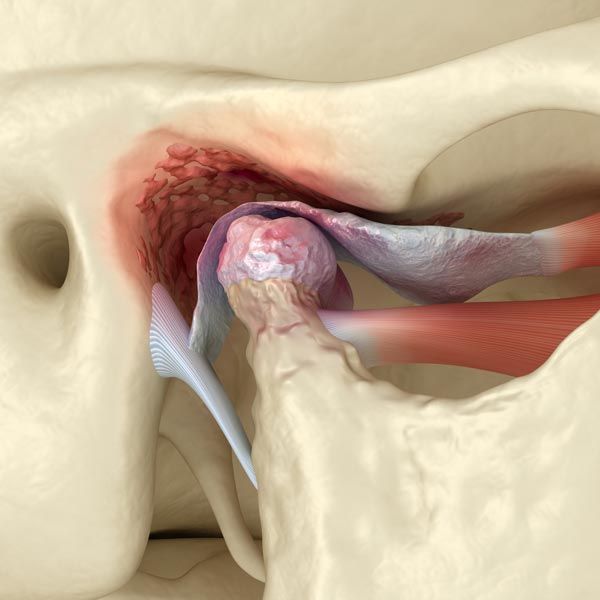

Here's What Your TMJs Look Like